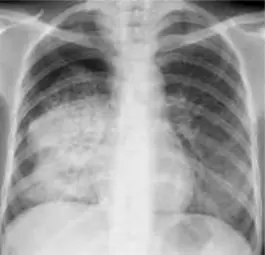

On a chest radiograph there will be shadowing, which may be in the form of patchy solid lesions, cavitated solid lesions, or streaky fibrotic flecks of calcification.

Image - Chest radiograph showing the shadowing seen in primary pulmonary TB. It shows the inflammation contained to one area (the right lower and middle lobes)

Creative commons source by "The Radiological Diagnosis of Pulmonary Tuberculosis (TB) in Primary Care". Journal of Family Medicine and Disease Prevention 4, Basem Abbas Al Ubaidi [CC BY-SA 4.0 (https://creativecommons.org/licenses/by-sa/4.0)]